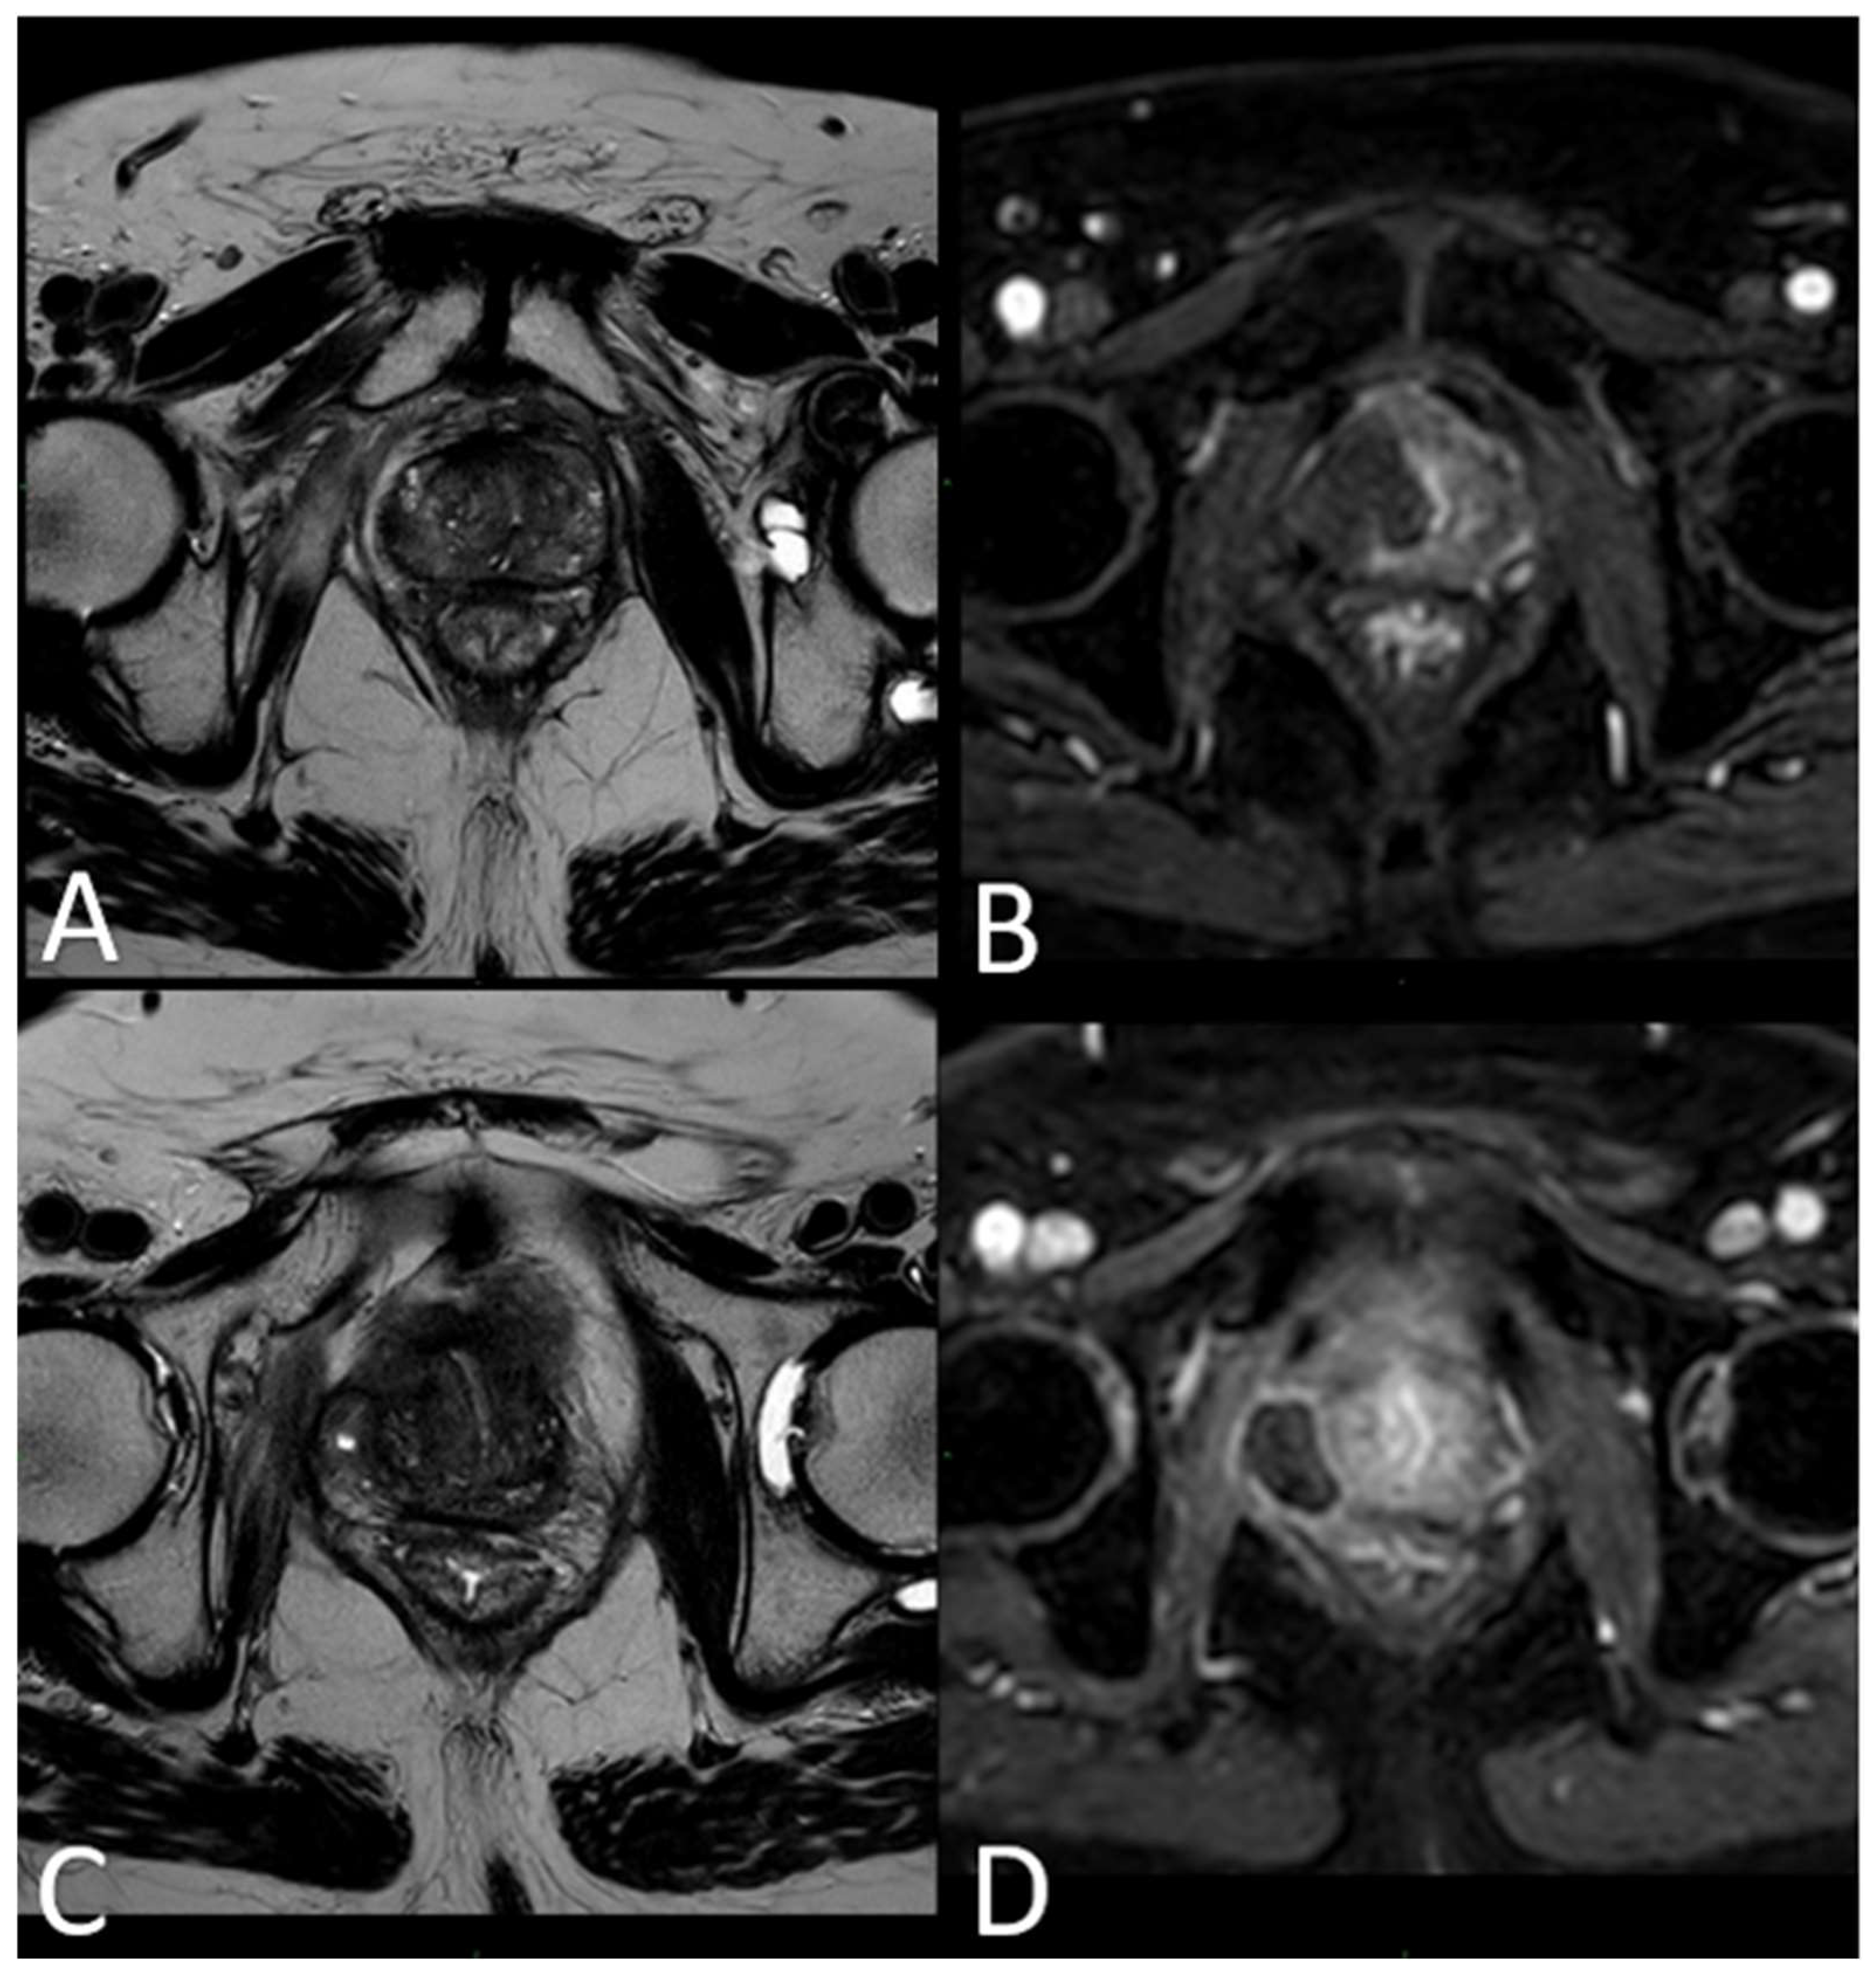

Immediate post-treatment mpMRI examinations consistently revealed the presence of a devascularized ablation cavity characterized by coagulative necrosis in all cases, and notably, this cavity exhibited a volume approximately three times larger than the original cancer lesion (as illustrated in Figure 3).

Figure 3.

(A) T2-w TSE sequence on axial plane 1 h after the treatment: an elliptical ablation cavity superimposing the lesion, filled with blood derivates and fluid as a result of tissue ablation. (B) DCE T1-w Dixon sequence 1 h after the treatment: unenhanced cavity in the right peripheral zone. (C) T2-w sequence on axial plane at 1-month follow-up: much wider ablative lesion with core charring, a hyperintense thick rim of necrotic tissue with an outer hypointense thin rim of hemorrhage. Fiber tracks are visible as hyperintense spots. Bulging of the capsule and liponecrosis on the right recto-prostatic triangle. (D) DCE T1-w Dixon sequence on axial plane at 1-month follow-up: unenhanced ablation cavity with a thick margin.

Immediately following the procedure, we observed elliptical hypointense ablation cavities that were roughly three times the size of the original lesions. Some of these cavities contained fluid and/or complex fluid (comprising blood and proteinaceous material), with hyperintense fiber tracks discernible within the treated area (as depicted in Figure 3A,B).

At 1 month–6 months–12 months: The main findings included the laser fiber tracks surrounded by a large elliptical-shaped necrotic tissue cavitation, which appeared hypointense on T2-weighted images (Figure 3C,D and Figure 6).

Figure 6.

(A) T2-w sequence on axial plane: coagulation necrosis area (hypointense in T2W imaging) is smaller because of necrotic tissue reabsorption. (B) DCE T1-w Dixon sequence: The unenhanced devascularized area (hypointense in T1W + C imaging) is smaller in size compared with the 1st-month MR follow-up.

At 24 months–36 months: presence of a T2W hypointense scar tissue that almost completely replaced the original cavity (Figure 5).